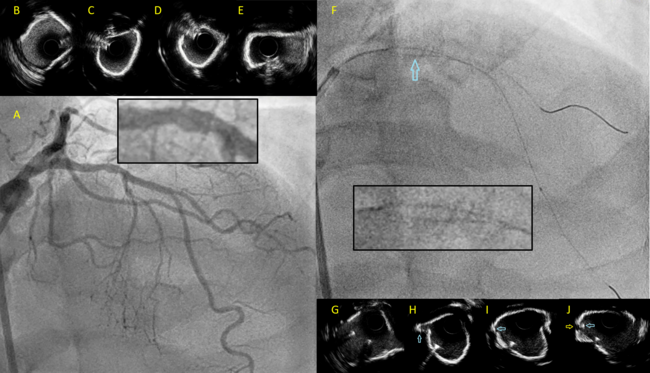

The proximal to mid-LAD had diffuse moderate to severe stenosis (Figure A), with intravascular ultrasound (IVUS) demonstrating eccentric superficial calcification of the proximal LAD followed by a short segment of near concentric calcification at the bifurcation with the major diagonal (Figure B-E).

After wiring both the LAD and the diagonal, the proximal LAD was pre-dilated with a 3.0-mm noncompliant balloon (Figure F). After balloon dilatation, we were unable to deliver any device (IVUS, balloon, guide extension catheter) over the diagonal wire due to heavy resistance at the proximal LAD.

IVUS interrogation over the LAD wire revealed a crack in the calcium parallel to the diagonal wire, with a short segment of the diagonal wire entrapped between 2 shelves of superficial calcium (Figure G-J; Video). The diagonal branch was rewired with a dual lumen microcatheter mounted on the LAD wire. There was no further resistance when delivering balloons on the new diagonal wire. The procedure was completed with 2 drug-eluting stents from the proximal to mid-LAD with a good result.